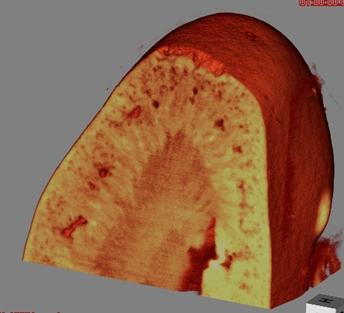

マウス心臓

結晶干渉法

17.8 keV

30秒

(投影像)

試料提供:北里大学Lwin准教授